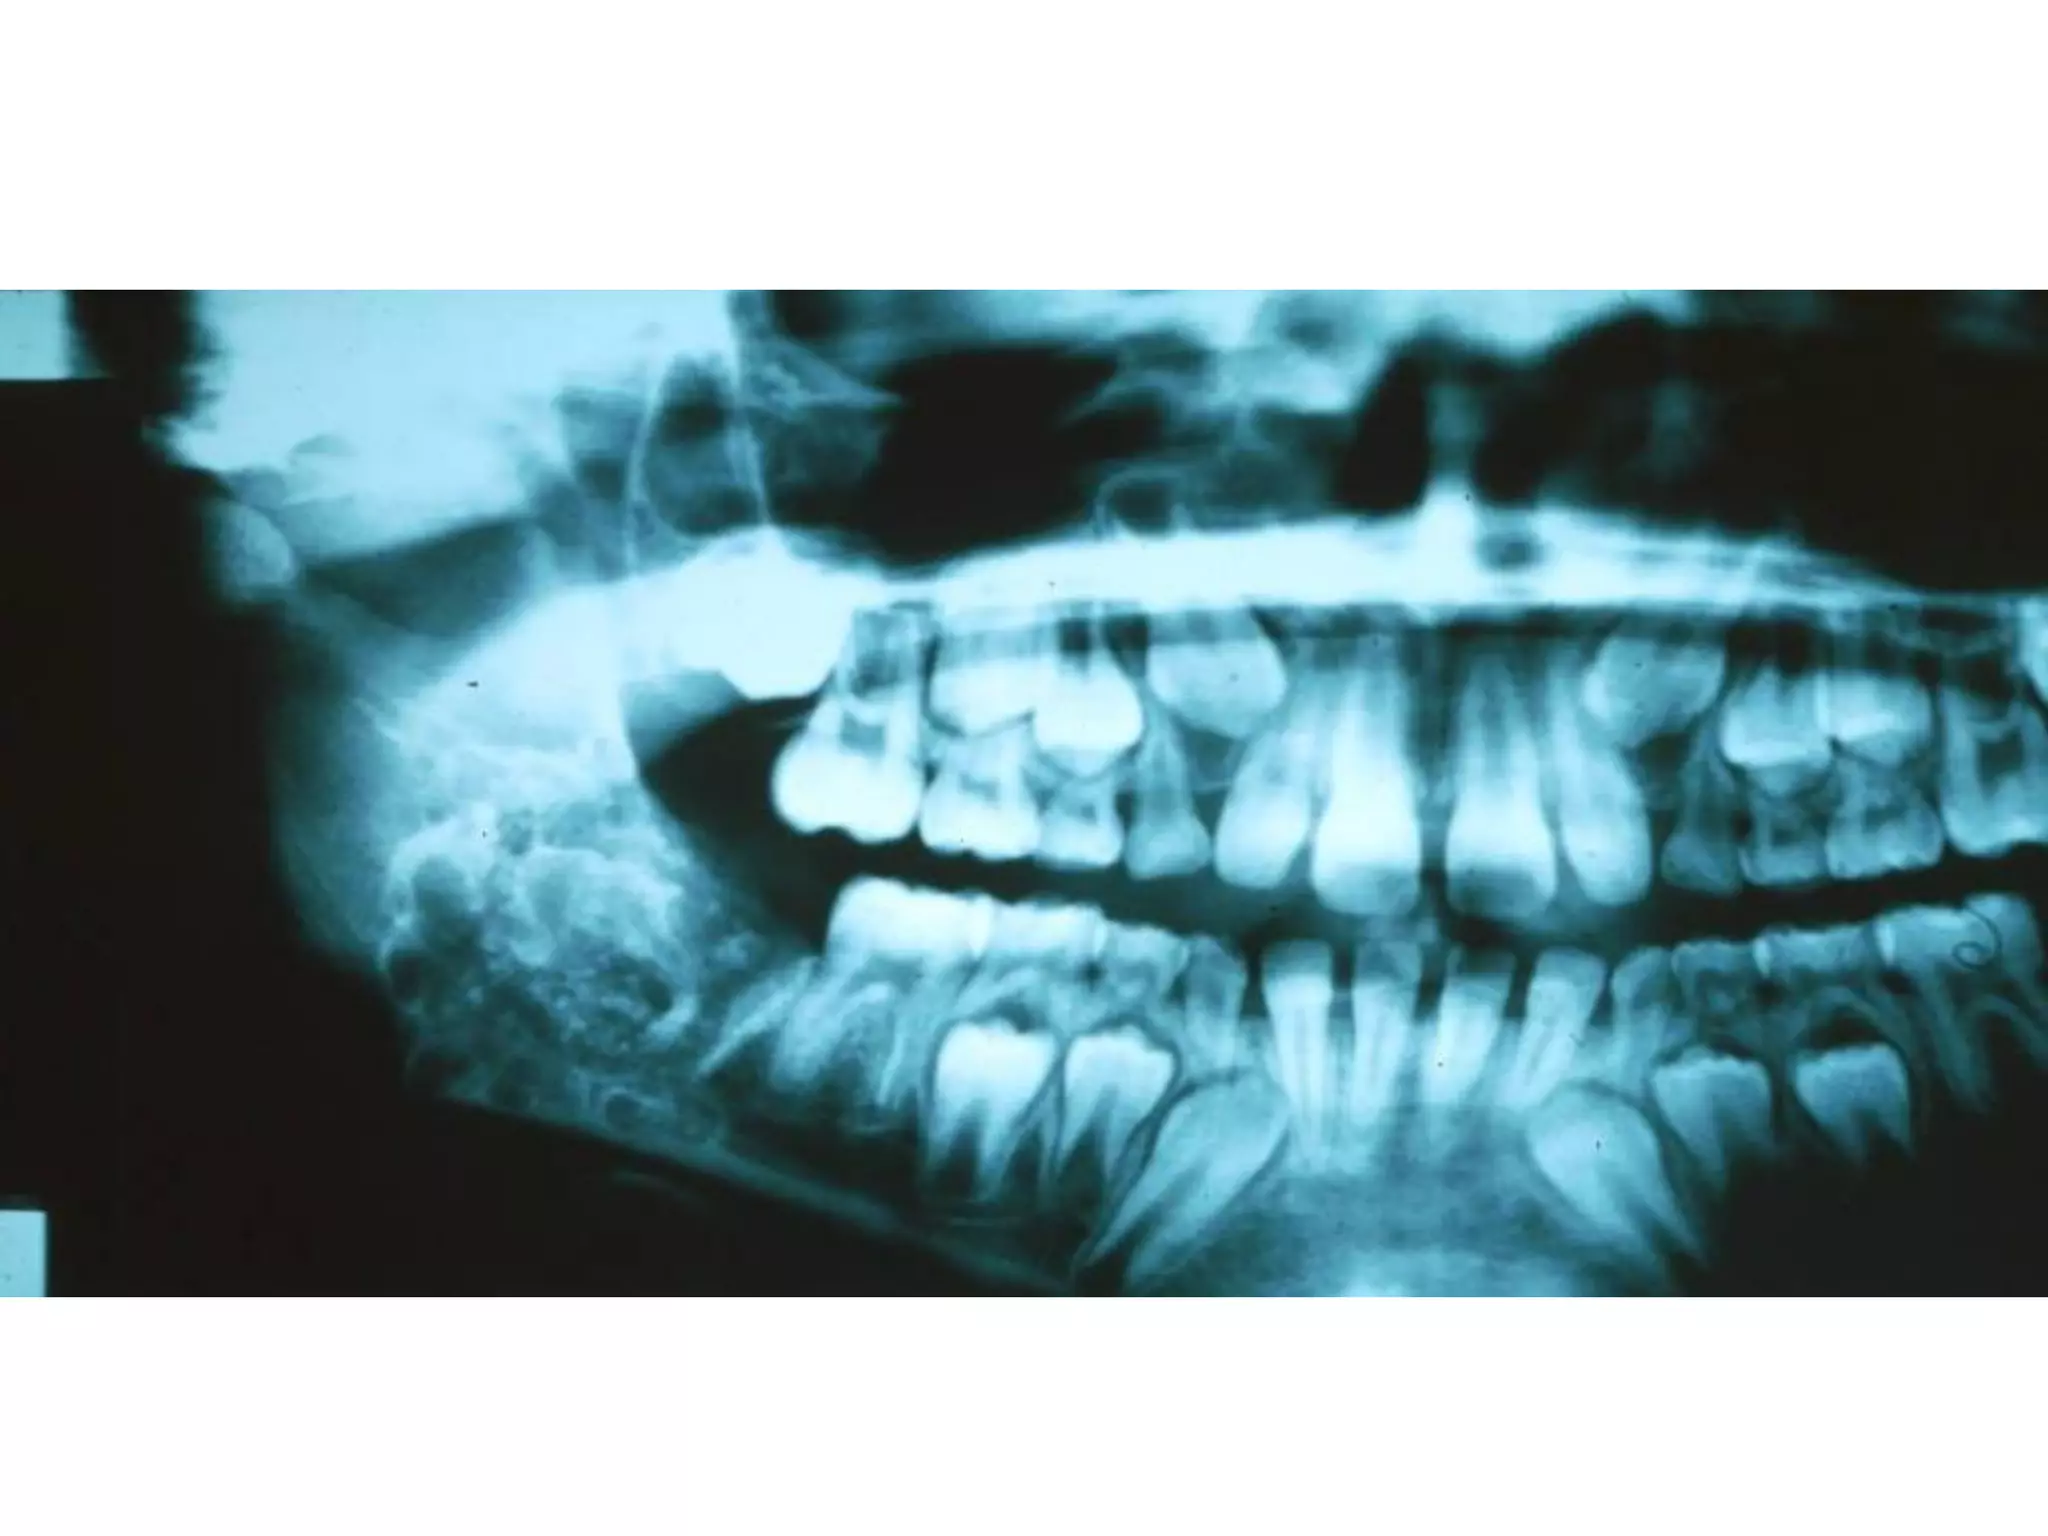

Ameloblastoma: daïng ñaëc hay ña

nang

Laâm saøng

 Tuoåi: 30-70.

 Giôùi: 2 giôùi nhö nhau.

 Vò trí: 80% XHD; 70% ôû vuøng R sau HD.

X quang: toån thöông thaáu quang thöôøng coù ranh giôùi roõ;

coù theå moät hoác hay nhieàu hoác (boït xaø phoøng, toå ong);

thænh thoaûng u coù ranh giôùi khoâng roõ, bôø nham nhôû.